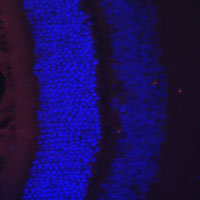

Immunofluorescent analysis of RDH5 staining in rat retina. Formalin-fixed cells were permeabilized with 0.1% Triton X-100 in TBS for 5-10 minutes and blocked with 3% BSA-PBS for 30 minutes at room temperature. Cells were probed with the primary antibody in 3% BSA-PBS and incubated overnight at 4 °C in a humidified chamber. Cells were washed with PBST and incubated with a AF594-conjugated secondary antibody (red) in PBS at room temperature in the dark. DAPI was used to stain the cell nuclei (blue).